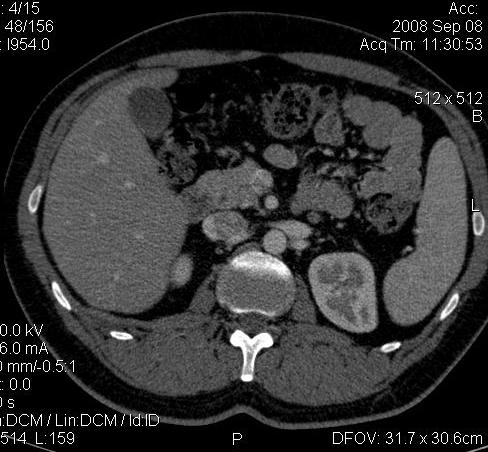

КТ Почек- подкова и уретеролитиаз

Ну ладно, раз никто больше не хочет, то отвечу свою версию - аномалия развития - подковообразная почка (horseshoe kidney).

Да красивая подковообразная почка - встречала раз 6-7.

Не вызывает сомнений. Картинка замечательная. Должно быть хорошо видно и на УЗИ.

Для невладеющего КТ,очень четка видна аномалия на 3-4х снимках.А вот на 4-м скане в проксим.сегменте цистоида тоже есть гиперденсное точечное образование-не камень случайно?